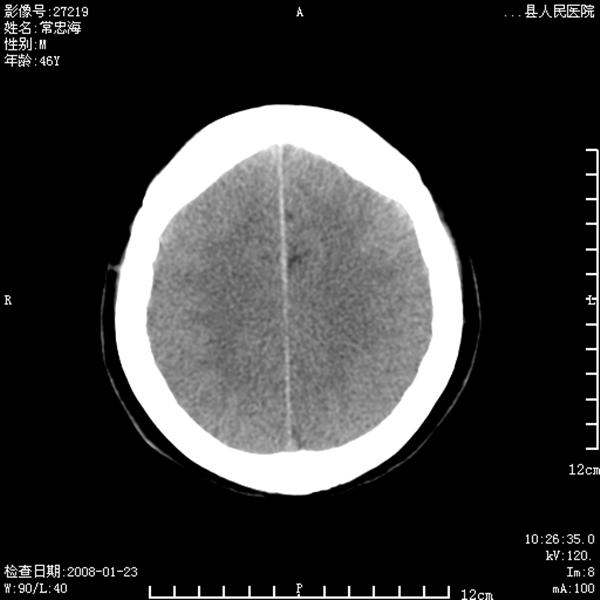

以下是引用江边学者在2008-4-19 22:26:00的发言:[br]1.胼胝体发育不良。[br]2.右侧眼球痨。[br]3.右侧颜面部软组织挫伤。